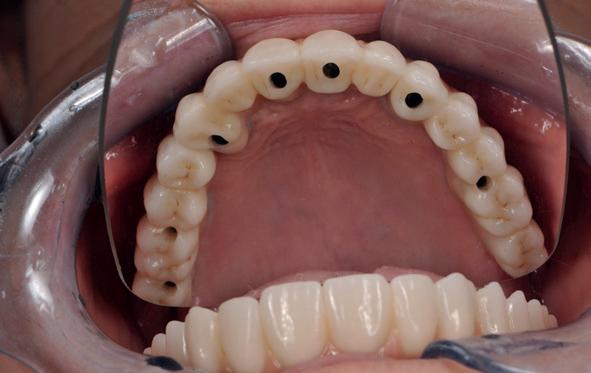

Een patiënt die conventioneel tandheelkundig vrijwel volledig is uitbehandeld, stelt de behandelaar voor complexe keuzes. In dit artikel wordt aan de hand van een uitgebreide casus beschreven hoe diagnostiek, prognosebepaling en interdisciplinair overleg leiden tot een voorspelbaar implantologisch behandeltraject. De casus illustreert hoe een ogenschijnlijk onsamenhangende restauratieve voorgeschiedenis kan uitmonden in een doordacht en succesvol full-arch implantaatgedragen rehabilitatieplan.

In de prothetische fase (zie foto’s) is in de bovenkaak gebruikgemaakt van verschroefde zirconia bruggen, die enkel buccaal zijn opgebakken. Deze bruggen zijn verlijmd op individuele, geanguleerde titanium abutments. In de onderkaak is een verschroefde kunststofbrug op een titaniumbasis (wrap-around) gemaakt. Voor deze combinatie is gekozen vanwege een minder hinderlijk tikkend geluid bij functie en kleinere kans op breuk van de keramiek. Een nadeel is verhoogde slijtage van de kunststof elementen, maar deze zijn in de jaren later eenvoudig te vervangen op de bestaande brug. Ondanks alle digitale mogelijkheden is de afdruk en registratiefase analoog uitgevoerd, omdat in ervaring van de behandelaren dit bij deze totale rehabilitaties op implantaten nog altijd de grootste precisie oplevert. Er is afgedrukt met impregum in individuele lepels en de pasvorm is gecontroleerd met rigide duralay bars. De relatie wordt vastgelegd zoals bij een volledige prothese met waswallen en pijlpuntregistratie. De opstelling in was wordt gepast en laatste correcties worden gemaakt in samenspraak met de patiënt, de restauratieve tandarts en de tandtechnicus. Na het vastzetten van de suprastructuren worden de schroefgaten afgesloten met composiet.

10. In de bovenkaak is gekozen voor 3 zirconium bruggen; in de onderkaak is gekozen voor een wrap-around met titanium

core.

11. In de bovenkaak is keramiek gebruikt en in de onderkaak kunststof (behandeling is